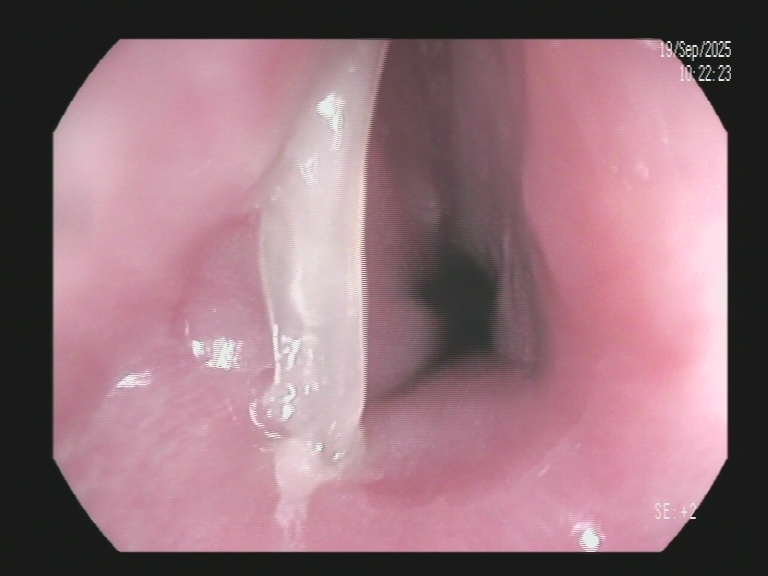

经胸部CT检查,明确诊断为食管内异物。情况较为棘手,因为患者自行处理的行为已导致长约3厘米的鱼刺横向卡于食管管腔,两端尖锐处深深扎入食管壁,扎入深度超过1厘米,造成局部黏膜严重损伤,极大地增加了食管穿孔、感染和出血的风险,也使得取出操作变得复杂。

面对这一危急情况,凤凰医院消化内科医疗分中心曹传坤院长迅速带领内镜团队,与麻醉团队紧密协作,制定了周密的无痛胃镜下异物取出方案。术中,发现鱼刺嵌顿牢固,常规方法难以取出。团队临危不乱,凭借丰富的经验和精湛的技术,使用专用器械谨慎操作,将鱼刺成功夹断,最终将其完整取出,彻底解除了患者的痛苦。